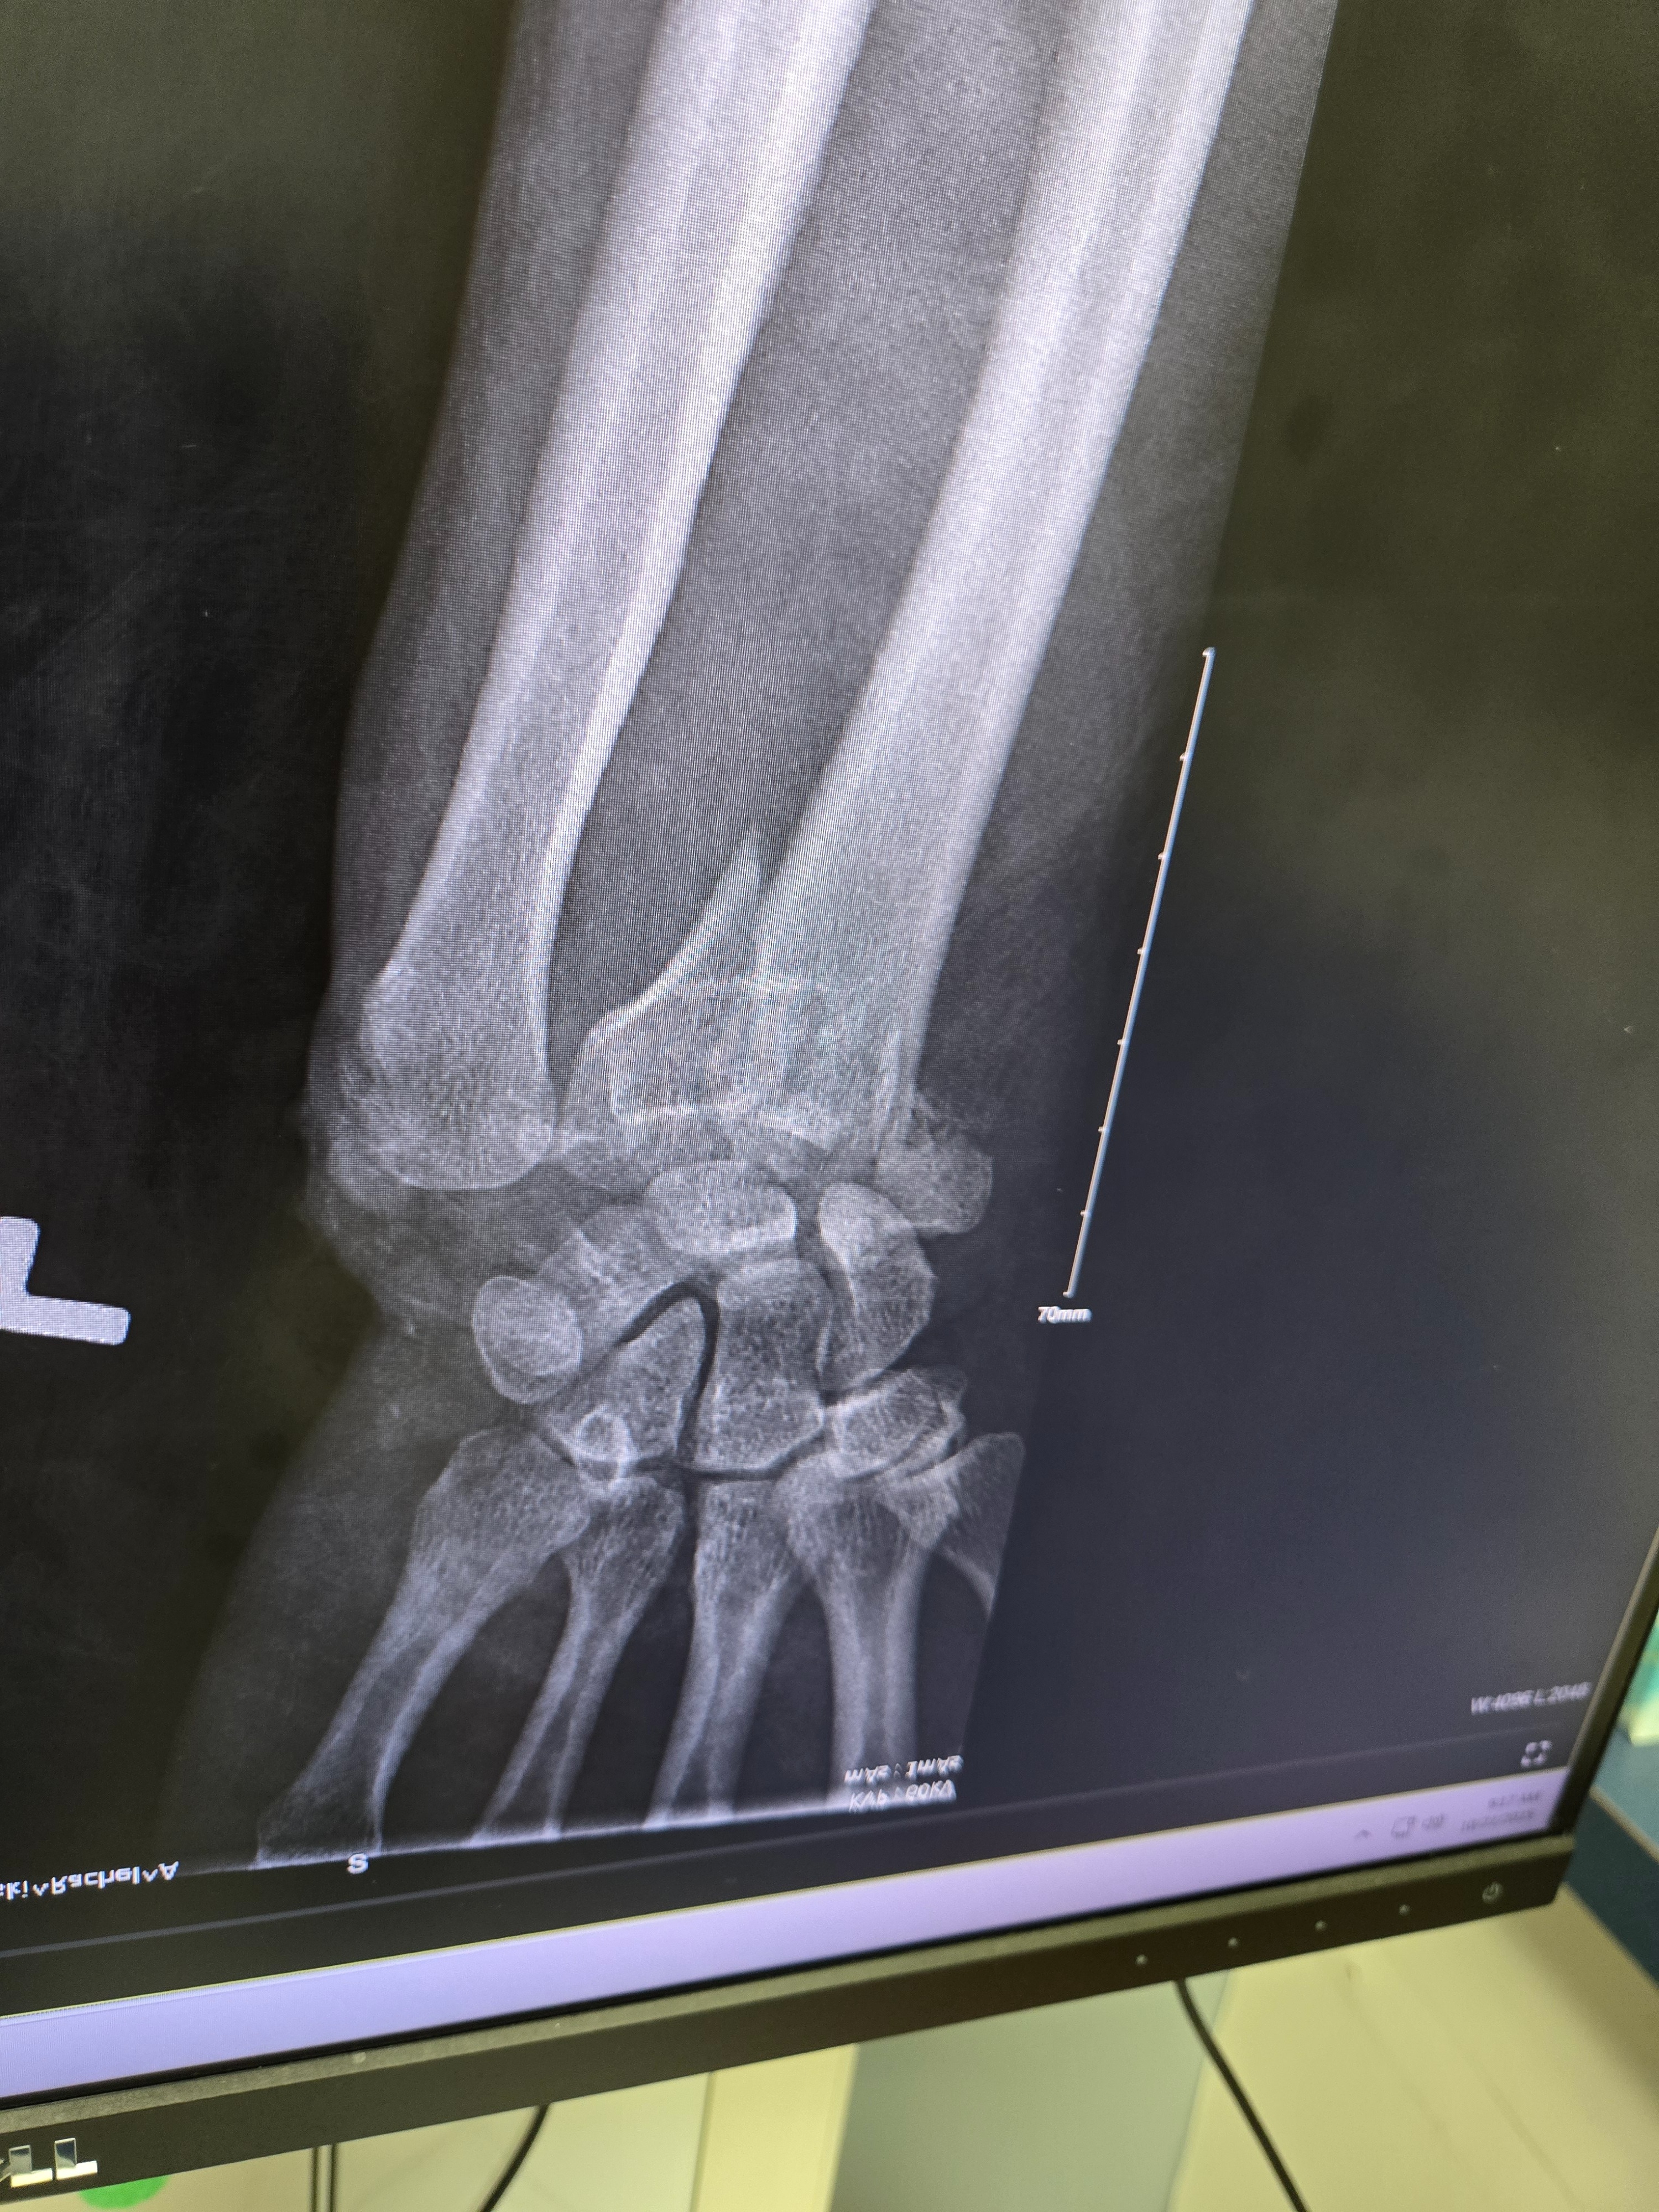

I SURVIVED!!!! My name is Rachel Blackowski, 31 years young.. I was in a severe car accident on Oct 4th . Spent a week in the hospital and have been in rehab. Broken wrist on the left hand (& I'm a lefty) Broken right leg, ankle and knee, non weight bearing injuries for both have me in the wheelchair for an estimated 12 weeks. Have gone through 3 surgeries so far with more to come. Looking at a 6-8 months minimum recovery. Unable to work to provide living wages & owe medical bills. Usually I would be too stubborn & prideful to ask for help ... but this has humbled me to realize I need to lean onto others in my time of need and it is okay. Thank you for any help offered.